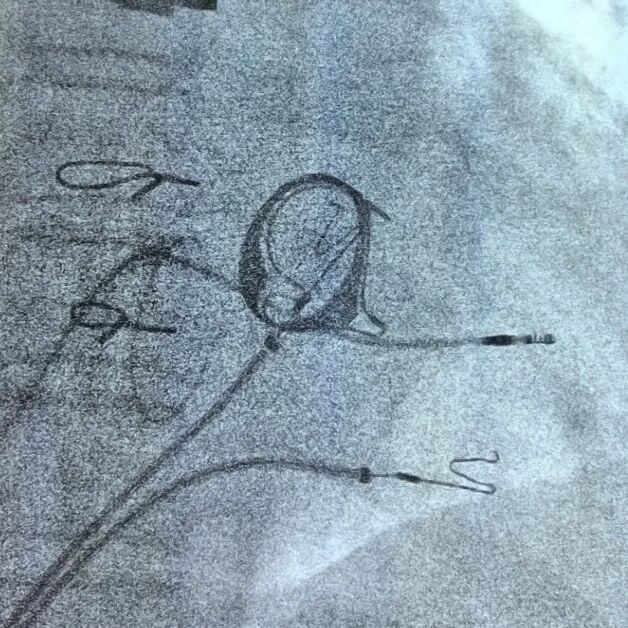

考虑患者有风湿性心脏病换瓣术、心功能不全和房颤伴慢心室率,术后起搏比例超过40%,单纯右室心尖或间隔起搏可能引起或加重心功能不全;经术前手术组讨论并经患者及家属知情同意决定于2025-09-15行左束支起搏植入术。手术成功行左侧腋静脉穿刺成功后,标准方法置入预制间隔弯鞘(K鞘)和电极;因为右房巨大支撑鞘无法到位,电极无法得到鞘的支撑,电极无法旋入左束支区域,术中操作近一小时,常规标准方法行左束支区域电极植入失败(图1),如果行右侧间隔植入,这样患者无法从这一先进起搏技术中获益;单其俊教授建议根据这个患者心脏特殊情况,用加硬(红色)导丝手塑3D间隔异型弯(根据患者心脏大小个体化量身定制)直接用ABBOTT普通心室螺旋电极进行左束支植入,通过20分钟艰难努力手术终于成功(图2),所有起搏参数满意(图3-5)。

图1 左图患者右房巨大,支撑鞘无法进入右室贴近间隔支撑电极旋入左束支区域,常规方法失败;右图根据患者心脏大小具体情况,用加硬(红色)导丝手塑3D间隔异型弯(量身定制)直接用普通心室螺旋电极旋入左束支区域,手术成功。